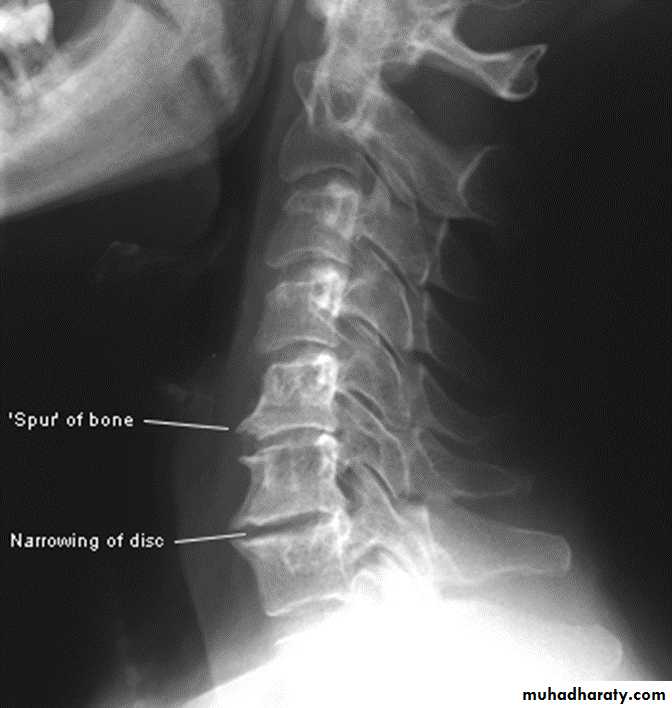

In the Spine :

* Lower cervical and low lumbar spine are most comonly affected.* Osteophytes may encroach on neural foramina (best seen on oblique views).

Cervical spondylosis